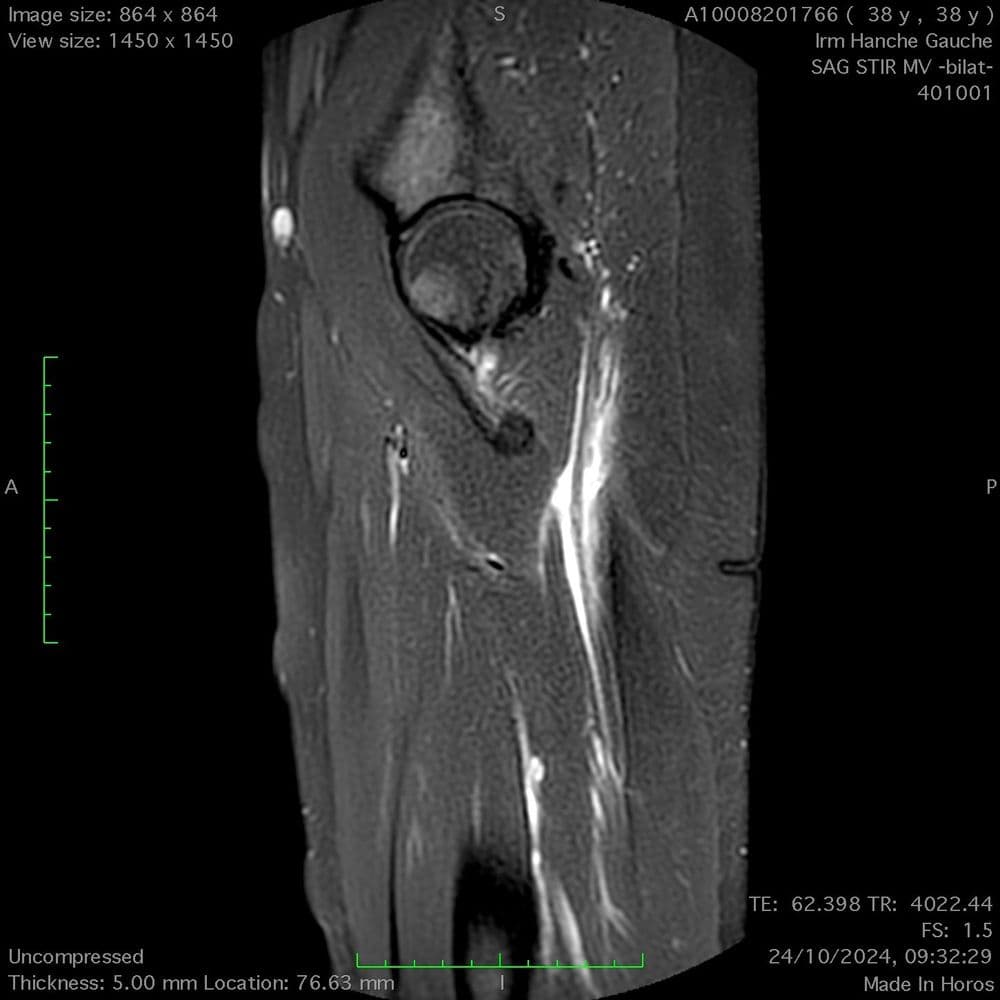

Conflit par réduction de l’espace entre le rebord ischiatique et la tête fémoral

MRI